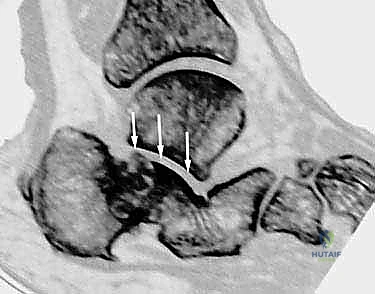

- الأشعة المقطعية ثلاثية الأبعاد (3D CT Scan): وهي الخطوة الذهبية والأهم في عيادة الدكتور هطيف. تتيح هذه الأشعة بناء نموذج ثلاثي الأبعاد دقيق للكعب المشوه، مما يسمح بتحديد أماكن الانحشار العظمي بدقة المليمتر، ومعرفة مدى تلف الأسطح المفصلية. بناءً على هذه الصور، يتم وضع خطة "القطع العظمي التصحيحي" قبل دخول غرفة العمليات.

- دمج المفصل تحت الكاحل (Subtalar Arthrodesis):

في الغالبية العظمى من حالات سوء الالتئام، يكون المفصل تحت الكاحل قد تدمر تماماً بسبب الخشونة والاحتكاك. الحل الجذري والنهائي للألم هنا هو "دمج" أو "تثبيت" هذا المفصل. يقوم الدكتور هطيف بتنظيف الغضاريف التالفة بالكامل، ووضع العظام في وضعها التشريحي الصحيح، ثم تثبيتها باستخدام براغي معدنية قوية جداً (Screws) لتلتحم وتصبح عظمة واحدة صلبة خالية من الألم.